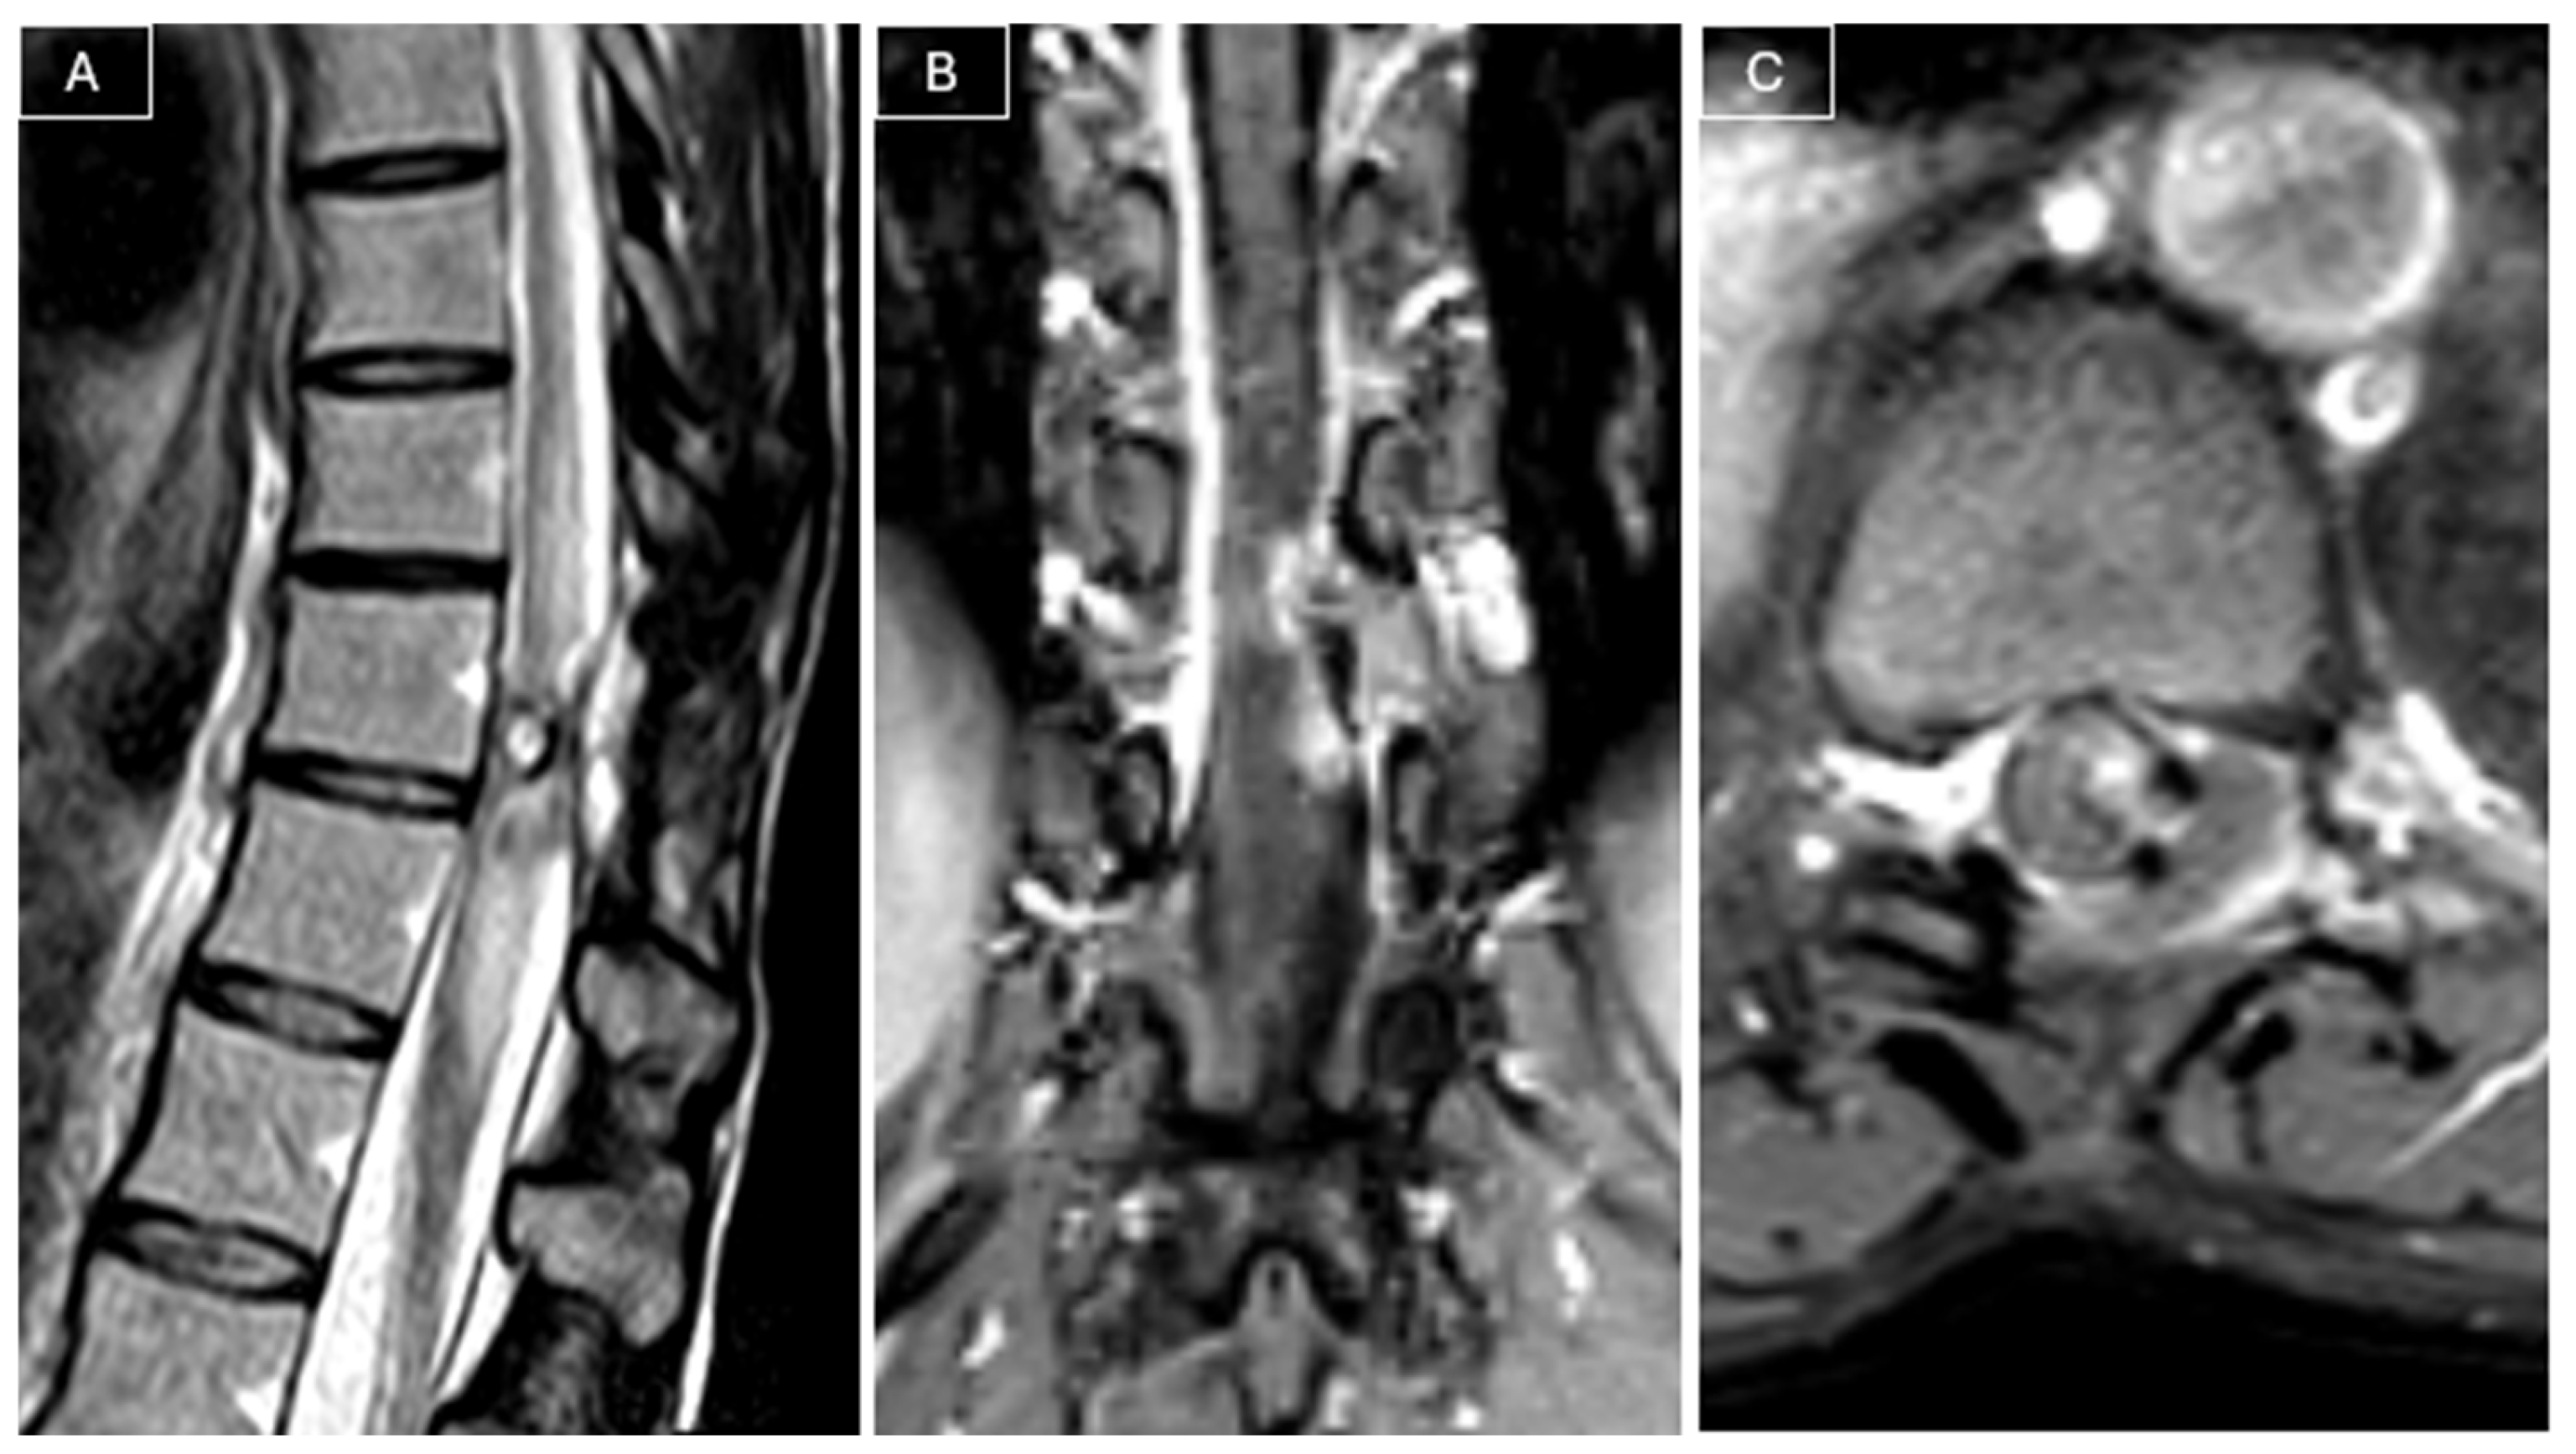

Magnetic resonance imaging (MRI) of the spine revealed a heterogeneously contrast-enhancing intra- and extracanalicular mass involving the left T10–T11 neural foramen. The lesion measured 21 × 8 × 21 mm and exhibited isointense signal on T1-weighted images and mildly hyperintense signal on T2-weighted images. The mass demonstrated both extradural and intradural components, compressing the spinal cord, and was initially considered a possible nerve sheath tumor given its location and partial extension into the neural foramen. (see Figure 1).

Figure 1. Preoperative MRI. (A) Coronal T2-weighted images demonstrated a heterogeneously hyperintense lesion compressing the spinal cord. The lesion appeared to have both intradural and extradural components and extended into the left T10–T11 neural foramen. (B) Sagittal T2-weighted images confirmed involvement of the left T10–T11 foramen by the tumor. (C) Sagittal post-contrast T1-weighted images showed the heterogeneous contrast enhancement of the lesion. The lesion appeared isointense on T1-weighted images (D) and slightly hyperintense on T2-weighted images (E).